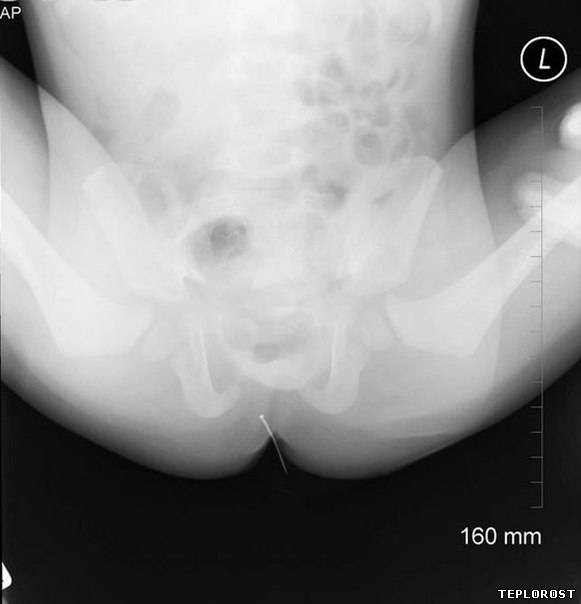

Обычная иголка в заднем проходе ребенка.